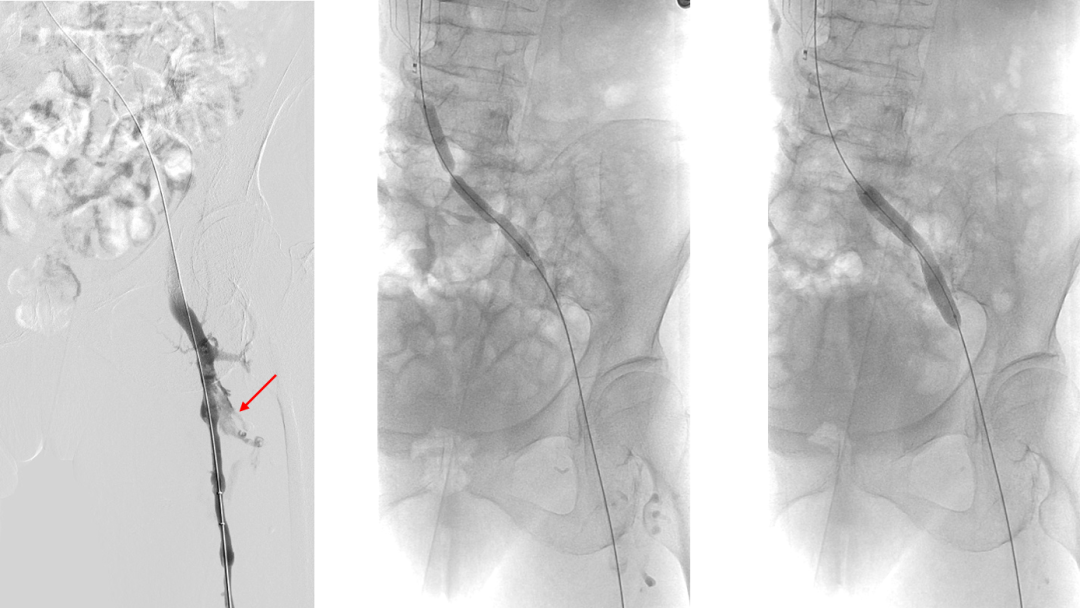

复查造影:股深静脉内血栓,股总静脉血流瘀滞,左髂静脉狭窄行PTA

Simon导管翻山后导丝进入股深静脉,造影明确股深静脉血栓范围

股深静脉吸栓后通畅,于左髂静脉置入14*80mm支架,复查造影血流均通畅

通过顺行与“翻山”双向入路结合,先顺行处理血栓和髂静脉狭窄,再“翻山”评估股深静脉血栓,避免了髂静脉狭窄合并血栓“翻山”困难、技术失败和手术时间明显延长

有效评估股深静脉血栓,一期行PMT清除,改善股总静脉及髂静脉支架流入道血流,提高髂静脉支架通畅率